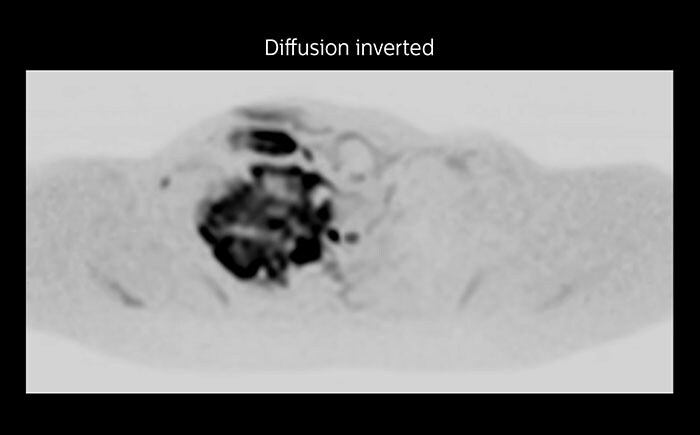

This patient is a 43-year-old female with a left supraclavicular nerve sheath tumor. The lesion is well visualized on the STIR VISTA images and on the MR neurography using DWIBS. The exam was performed on Prodiva 1.5T.

Acq voxel size 1.2 x 1.3 x 2.4 mm, Recon voxel size 0.7 x 0.7 x 1.2 mm, dS SENSE factor 2, scan time 5:46 min.